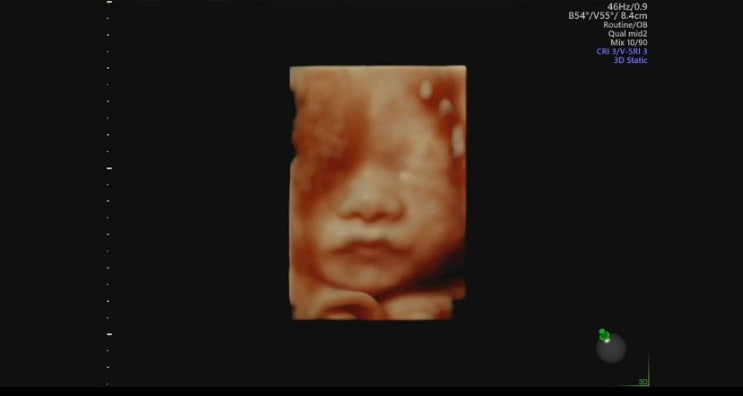

임신 27주차 0일 - 두근두근 일산차 입체초음파

#임신기록 #27주차 안녕하세요! 11월 14일 정기검진 다녀왔는데요 ❤️ 벌써 임신 27주차 두근두근 남편과 ...